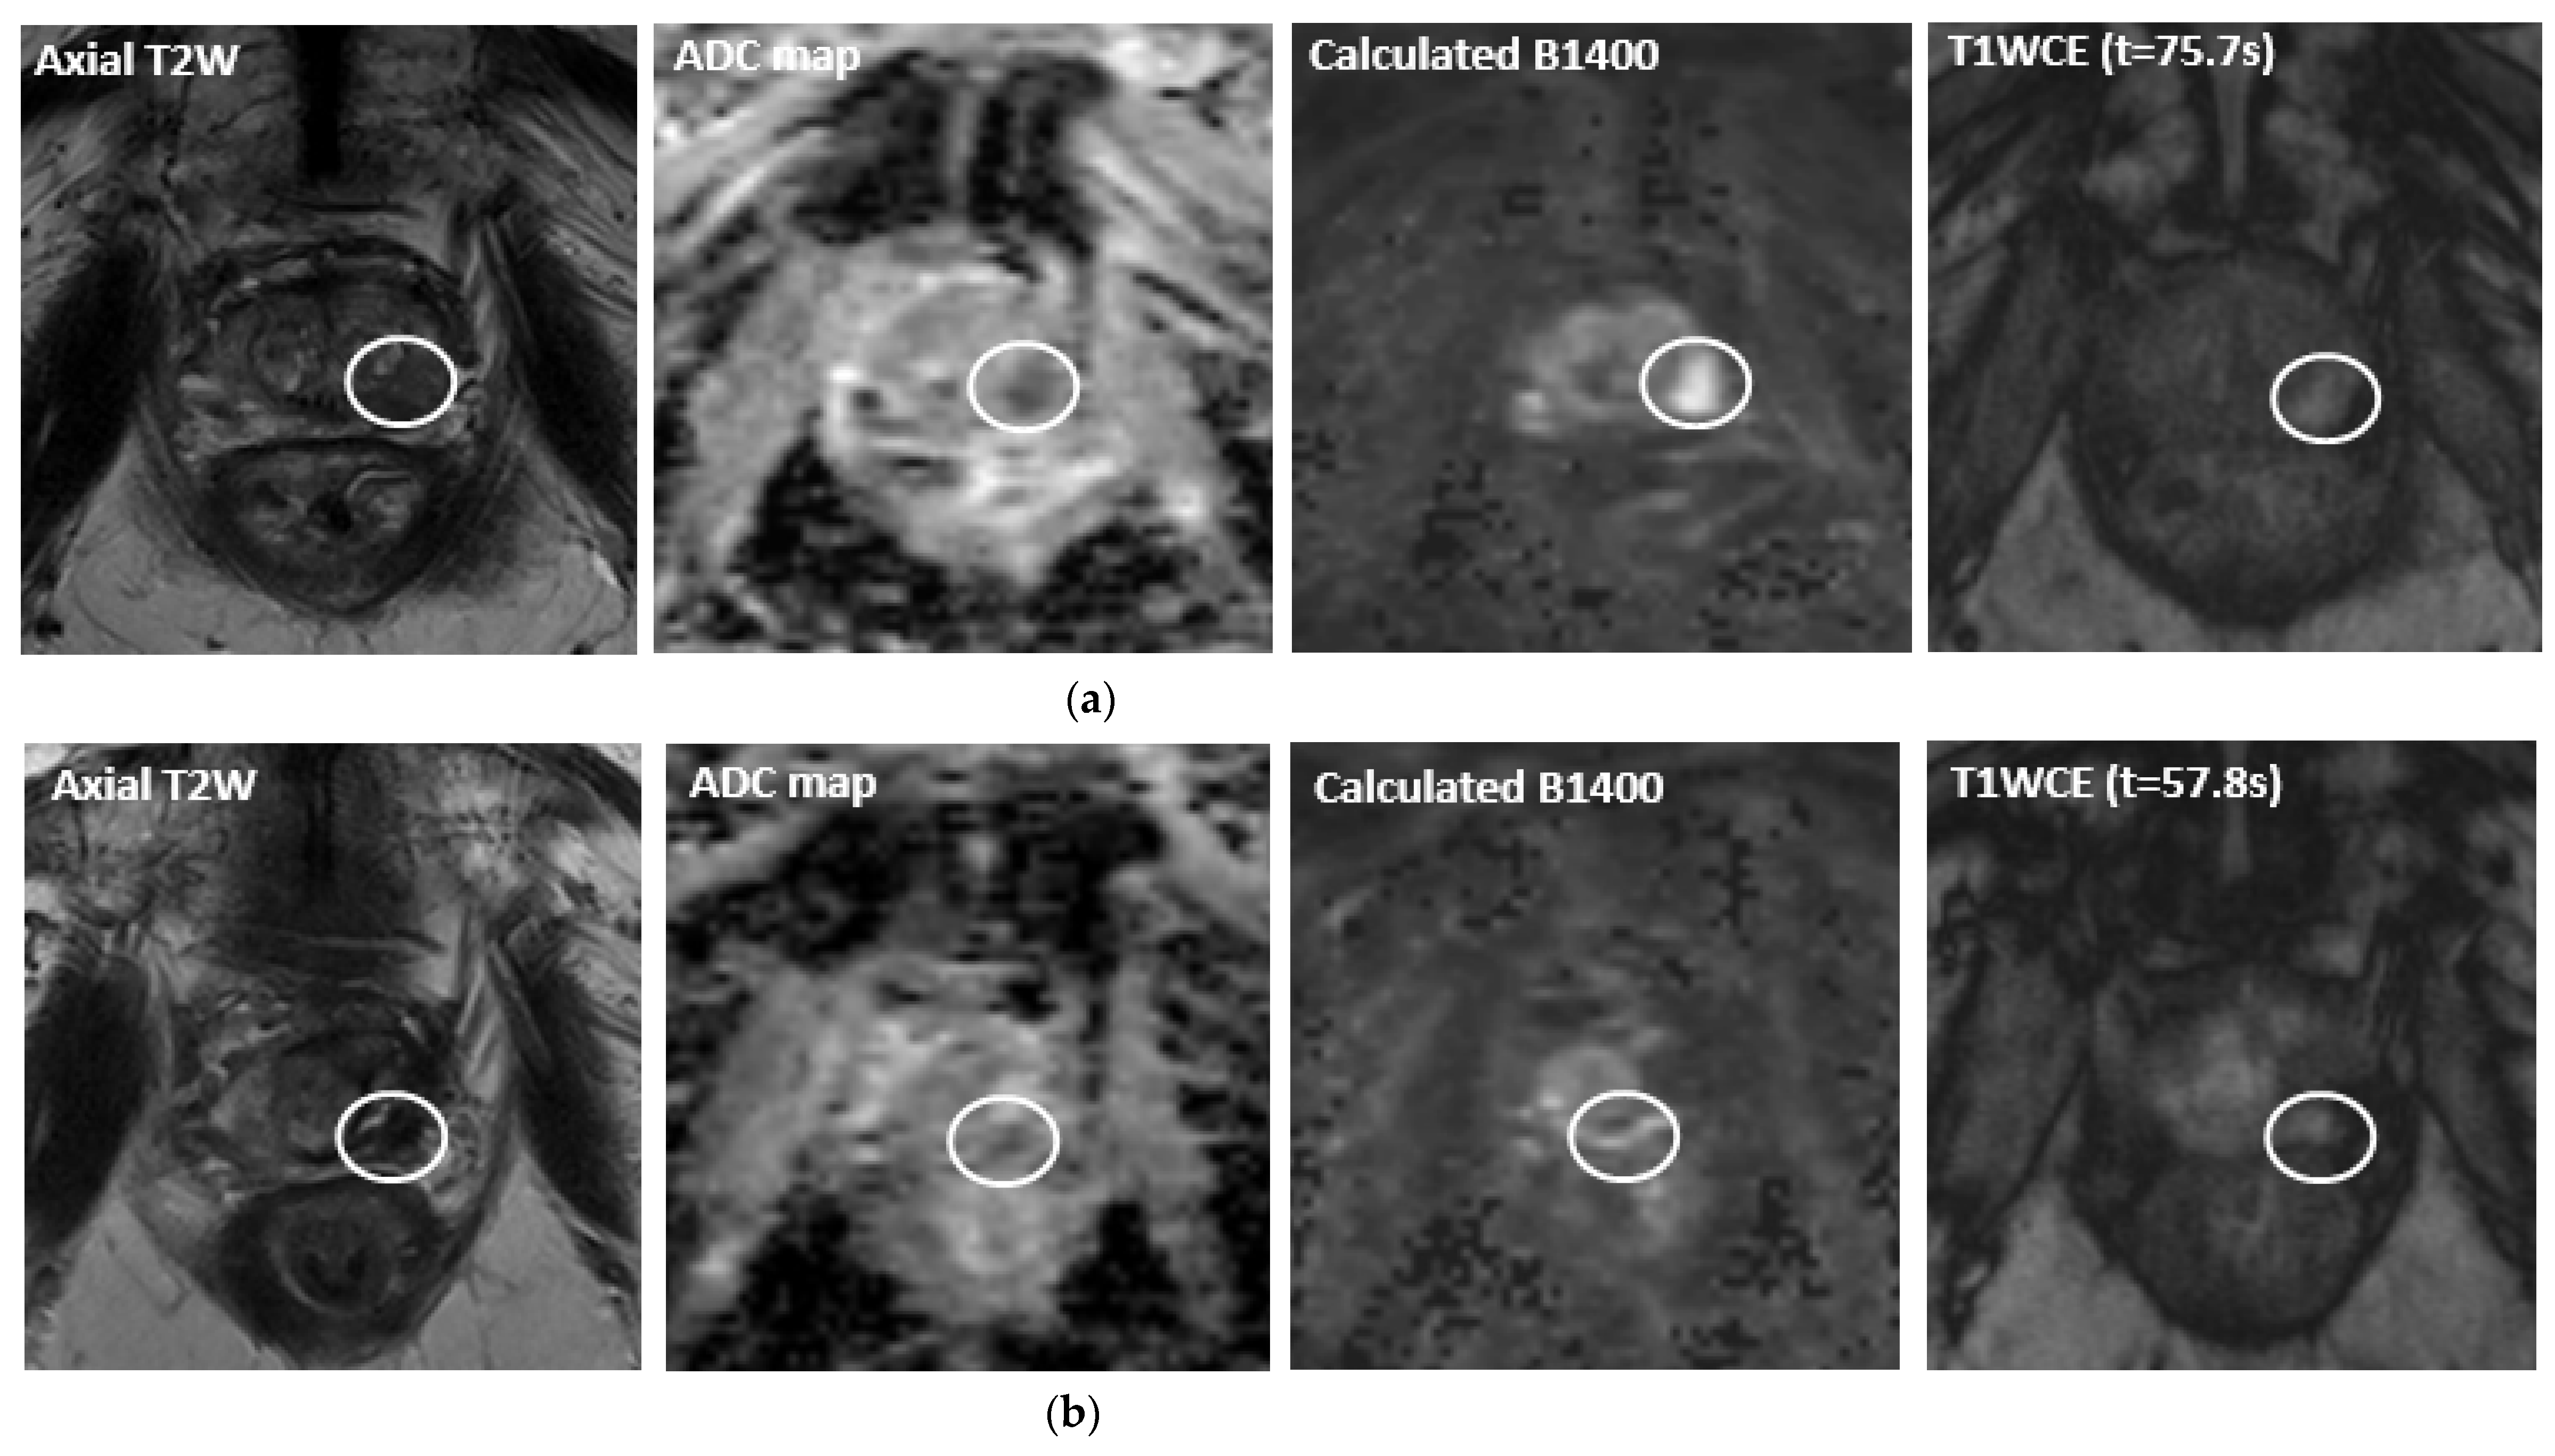

- Ramsay, E.; Mougenot, C.; Staruch, R.; Boyes, A.; Kazem, M.; Bronskill, M.; Foster, H.; Sugar, L.; Haider, M.; Klotz, L.; et al. Evaluation of Focal Ablation of Magnetic Resonance Imaging Defined Prostate Cancer Using Magnetic Resonance Imaging Controlled Transurethral Ultrasound Therapy with Prostatectomy as the Reference Standard. J. Urol. 2017, 197, 255–261. [Google Scholar] [CrossRef]

- Anttinen, M.; Mäkelä, P.; Suomi, V.; Kiviniemi, A.; Saunavaara, J.; Sainio, T.; Horte, A.; Eklund, L.; Taimen, P.; Sequeiros, R.B.; et al. Feasibility of MRI-guided transurethral ultrasound for lesion-targeted ablation of prostate cancer. Scand. J. Urol. 2019, 53, 295–302. [Google Scholar] [CrossRef]

- Anttinen, M.; Mäkelä, P.; Viitala, A.; Nurminen, P.; Suomi, V.; Sainio, T.; Saunavaara, J.; Taimen, P.; Sequeiros, R.B.; Boström, P.J. Salvage Magnetic Resonance Imaging–guided Transurethral Ultrasound Ablation for Localized Radiorecurrent Prostate Cancer: 12-Month Functional and Oncological Results. Eur. Urol. Open Sci. 2020, 22, 79–87. [Google Scholar] [CrossRef]